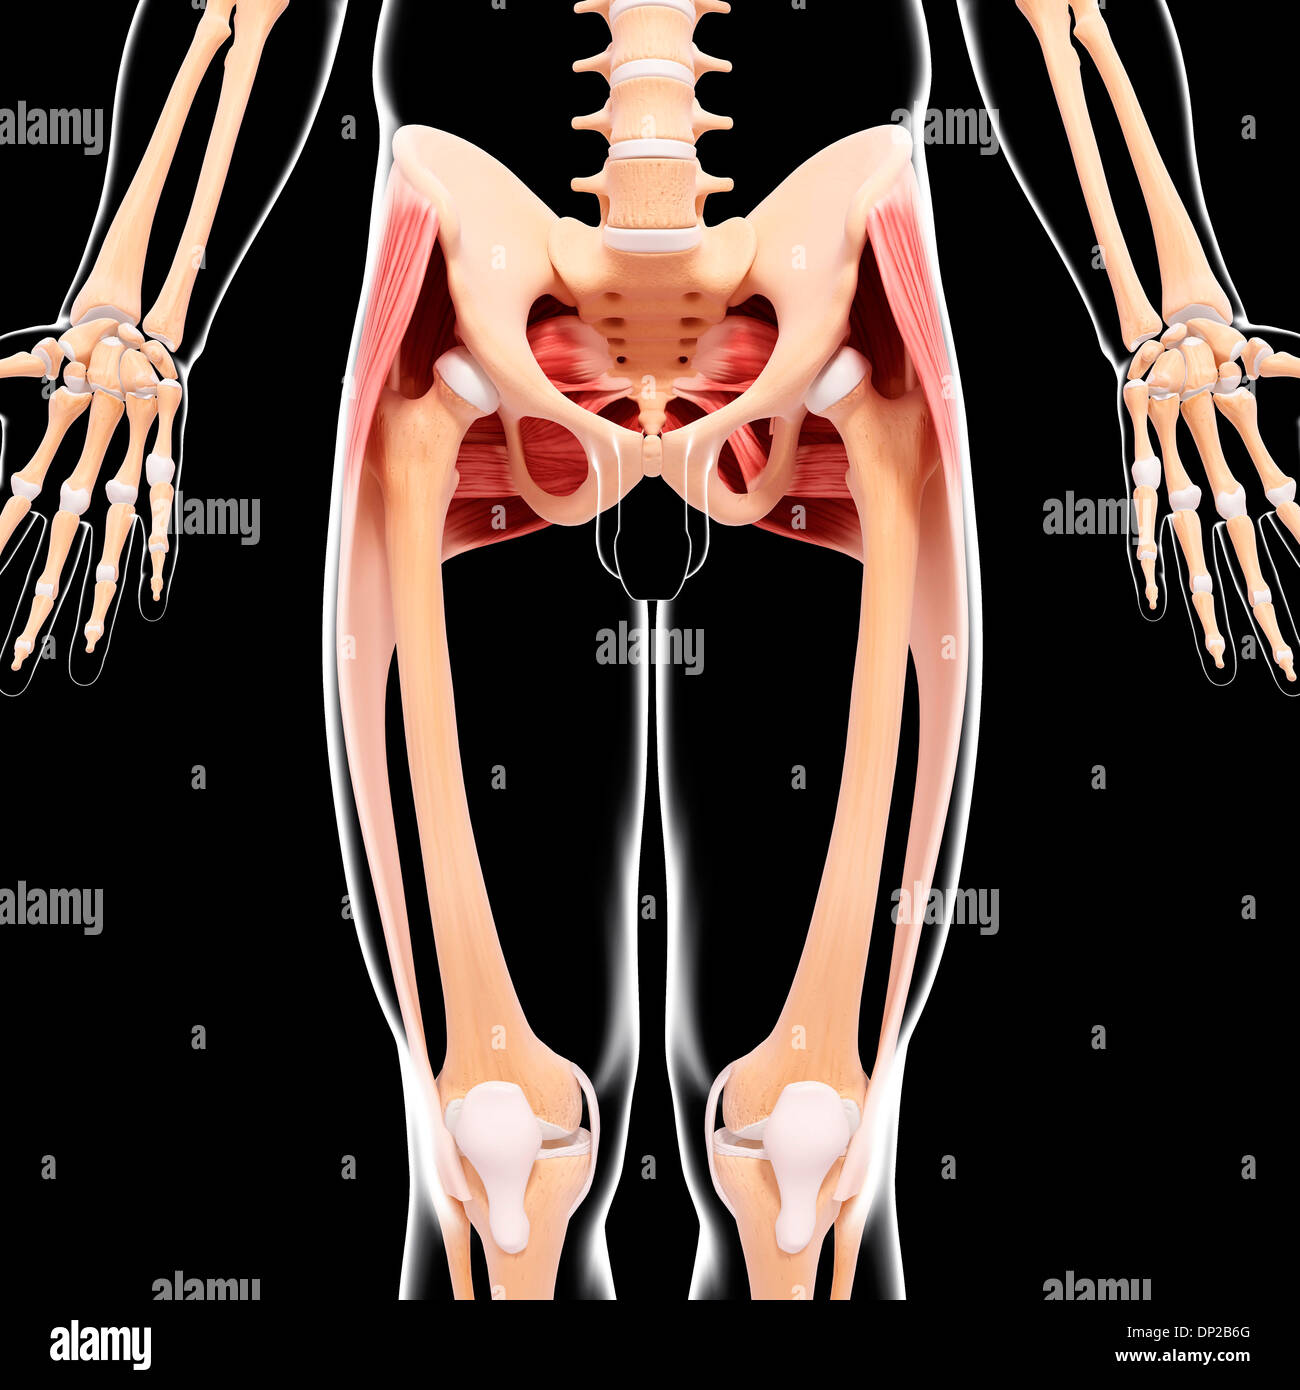

Human hip musculature, artwork Stock Photohttps://www.alamy.com/image-license-details/?v=1https://www.alamy.com/human-hip-musculature-artwork-image65206248.html

Human hip musculature, artwork Stock Photohttps://www.alamy.com/image-license-details/?v=1https://www.alamy.com/human-hip-musculature-artwork-image65206248.htmlRFDP2B6G–Human hip musculature, artwork